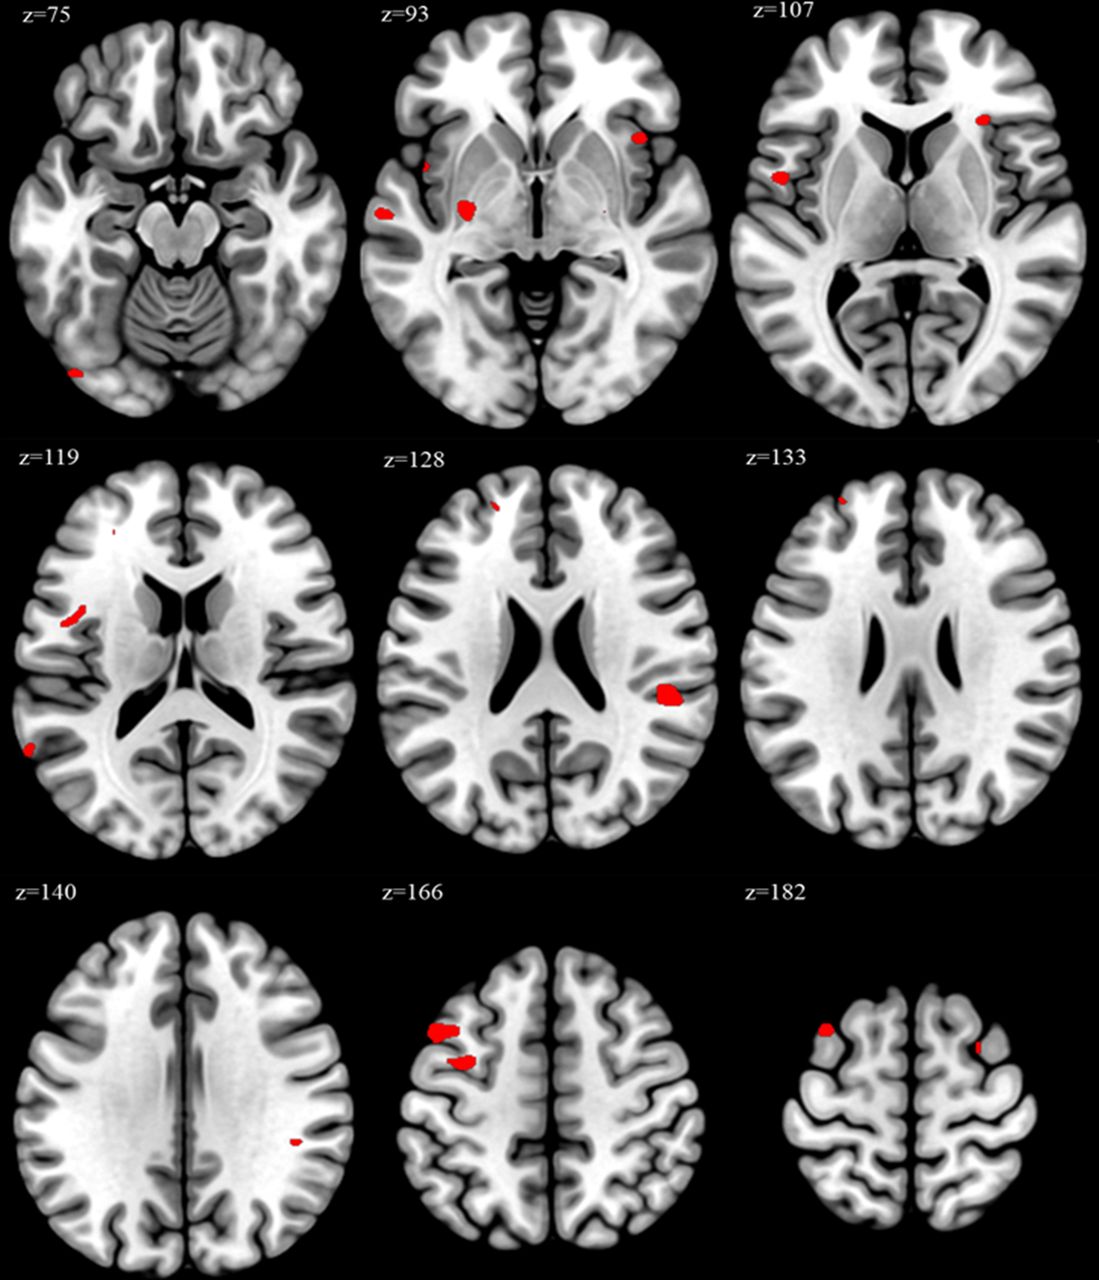

Йдеться зокрема про лобову звивину та острівець - зони, що впливають на нашу здатність концентруватися, спілкуватися, розуміти емоції та реагувати на стрес.

За словами одного з авторів дослідження, доцента Джуна Юла Чоя, ці зміни можуть бути частково оборотними , якщо прибрати хронічний стрес. Але на це потрібен час - мозок не відновлюється миттєво.

Науковці наголошують: постійне перепрацювання - це не просто втома, а реальна загроза для когнітивного й психічного здоров'я . І чим раніше людина почне зменшувати навантаження, тим більше шансів уникнути довгострокових змін.

Зміни в мозку, які відбувають при перепрацюванні (фото: oem.bmj.com)

Зміни в мозку, які відбувають при перепрацюванні (фото: oem.bmj.com)